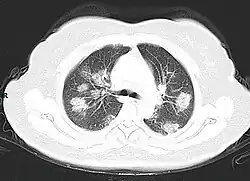

From the CT scans of COVID-19 infected lungs, white patches were observed containing fluid known as ground-glass opacity (GGO) or simply ground glass.[130] This tended to correlate with the clear jelly liquid found in lung autopsies of people who died of COVID-19. One possibility addressed in medical research is that hyuralonic acid (HA) could be the leading factor for this observation of the clear jelly liquid found in the lungs, in what could be hyuralonic storm, in conjunction with cytokine storm.[131]

Imaging

Chest CT scans may be helpful to diagnose COVID‑19 in individuals with a high clinical suspicion of infection but are not recommended for routine screening.[175][187] Bilateral multilobar ground-glass opacities with a peripheral, asymmetric, and posterior distribution are common in early infection.[175][188] Subpleural dominance, crazy paving (lobular septal thickening with variable alveolar filling), and consolidation may appear as the disease progresses.[175][189] Characteristic imaging features on chest radiographs and computed tomography (CT) of people who are symptomatic include asymmetric peripheral ground-glass opacities without pleural effusions.[190]

Many groups have created COVID‑19 datasets that include imagery such as the Italian Radiological Society which has compiled an international online database of imaging findings for confirmed cases.[191] Due to overlap with other infections such as adenovirus, imaging without confirmation by rRT-PCR is of limited specificity in identifying COVID‑19.[190] A large study in China compared chest CT results to PCR and demonstrated that though imaging is less specific for the infection, it is faster and more sensitive.[174]